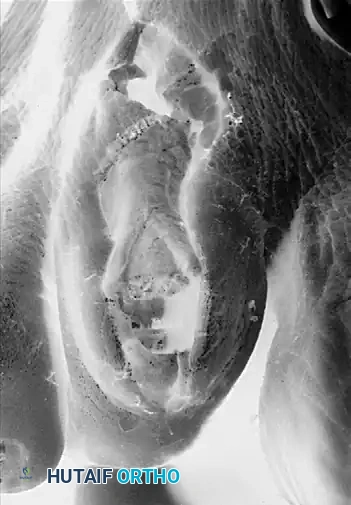

Intraoperative view of antegrade pinning through the proximal interphalangeal joint.

Diagrammatic representation: Pin inserted antegrade through the middle and distal phalanges.

Insert a 0.045-inch or 0.062-inch Kirschner wire antegrade through the remaining shaft of the proximal phalanx, passing it through the PIP joint, middle phalanx, and distal phalanx. The pin should exit in the midline, approximately 2 to 3 mm plantar to the nail bed.